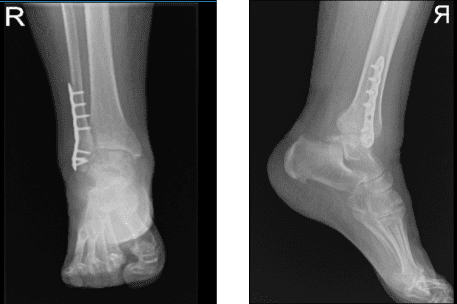

A 4-hole distal fibular plate was opted held with olive K-wires. Finding an acceptable position in AP and lateral view, fixation of the plate was done to the fibula using four cortical nonlocking proximal screws and four locking distal screws

After a month, suggested to the patient to take X-ray to see the condition of the operated ankle. Result showed old surgically treated healed distal fibular fracture. Patient not undergone Physical Therapy. With the consistent follow up checkup and RICE procedure, patients get well.